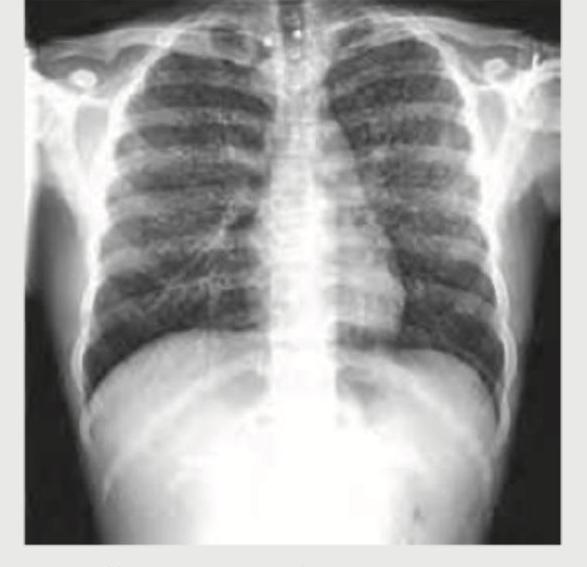

Question 2: A 40-year-old male presents with sudden onset right-sided chest pain and breathlessness following a road traffic accident. On examination, breath sounds are diminished on the right side. The chest X-ray is shown below. What is the most likely diagnosis?

- C. Right hydropneumothorax (Correct Answer)

Explanation: ***Right hydropneumothorax*** - The X-ray image reveals an **air-fluid level** in the right pleural cavity, characterized by a straight, horizontal line between the air (darker above) and fluid (whiter below). This finding is pathognomonic for a hydropneumothorax. - The **collapsed or compressed lung** is also visible superior to the air-fluid level, further supporting the diagnosis of air and fluid coexisting in the pleural space. *Hydatid cyst right lung* - A hydatid cyst in the lung appears as a **well-defined, rounded opacity (solid mass)**, often with a "water lily" sign if ruptured, but it does not present with a distinct air-fluid level as seen here. - While hydatid cysts can rupture and produce air and fluid, the X-ray findings would typically show a more complex internal structure or a cyst within a cavity, not a simple air-fluid interface across the entire pleural space. *Right pleural effusion* - A pleural effusion would appear as a **homogeneous white (effaced) opacity** blunting the costophrenic angle and, in larger effusions, rising along the lateral chest wall (meniscus sign). - Crucially, a simple pleural effusion **does not show an air-fluid level**; the fluid density would fill the pleural space without an overlying visible air component. *Perforated abdominal viscus* - A perforated abdominal viscus would typically result in **free air under the diaphragm** on an upright chest X-ray (pneumoperitoneum). - While pneumoperitoneum presents as air, it is located below the diaphragm, *not* within the pleural cavity, and would not create an air-fluid level within the lung fields as seen in this image.